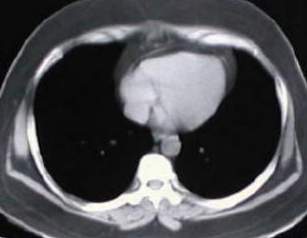

Tomografía torácica

• Estudios de tomografía del tórax, electromiografía, expirometría y prueba terapeutica con edrofonio, son realizados, concluyendo el diagnóstico de miastenia gravis con Timoma, (16 meses despues de iniciados los síntomas).